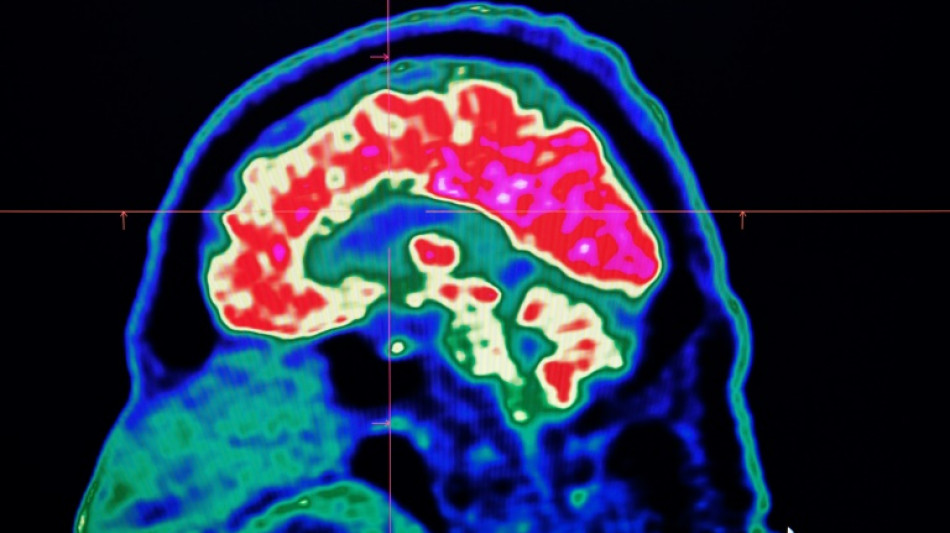

La inteligencia artificial reduce el riesgo de secuelas por un derrame cerebral / Foto: © AFP/Archivos

La inteligencia artificial ayuda en la toma de decisiones a la hora de interpretar los escáneres del cerebro y así permitir que los pacientes "reciban el tratamiento adecuado, en el buen lugar y en el buen momento", destaca el ministerio.